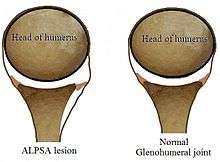

The shoulder joint is made up of the glenoid and humeral head. The humeral head is ball shaped but the glenoid is more dish shaped than cup shaped. To aid stability of the joint, the glenoid has a soft tissue bumper around its edge (the labrum) which acts as a bumper preventing dislocation of the head from the glenoid.

The anterior (front) labrum can peel off the glenoid resulting in a Bankart lesion. When the periosteum (fibrous tissue surrounding bone) peels off as well this is called an ALPSA lesion. When this happens the labrum (bumper) falls away and rolls up. It normally falls medially and downwards.